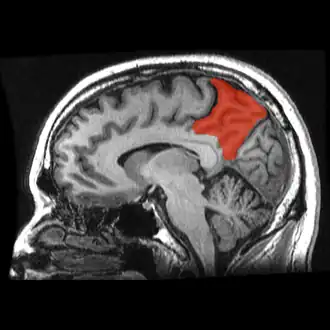

Sagittal MRI slice with the precuneus shown in red. (Anterior to the left.)